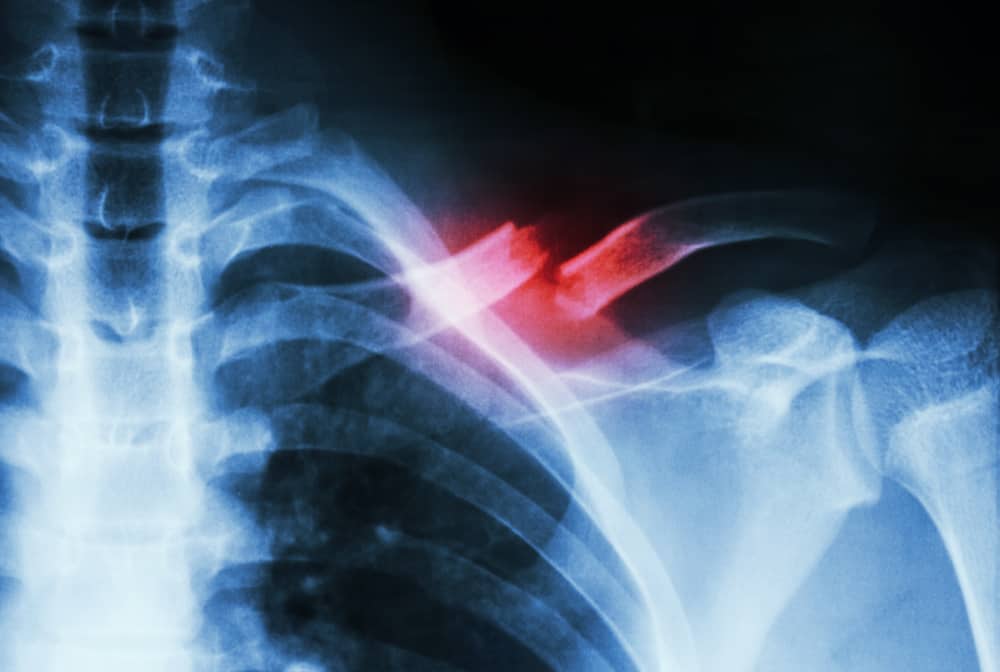

- Compound Fractures: When a bone breaks and pierces through the skin, it’s a compound fracture. X-rays can show the extent of bone displacement.

- Comminuted Fractures: If a bone shatters into multiple pieces, it’s a comminuted fracture. X-rays provide a detailed view of the scattered bone fragments.

When it comes to surgical interventions, X-rays act as an invaluable guide. They provide detailed images of the fracture, helping surgeons plan their approach. For instance, in cases of compound or comminuted fractures, where the bone is broken into multiple pieces, X-rays offer crucial insights into the location and orientation of these fragments. This information is vital for successful surgery and optimal patient outcomes.